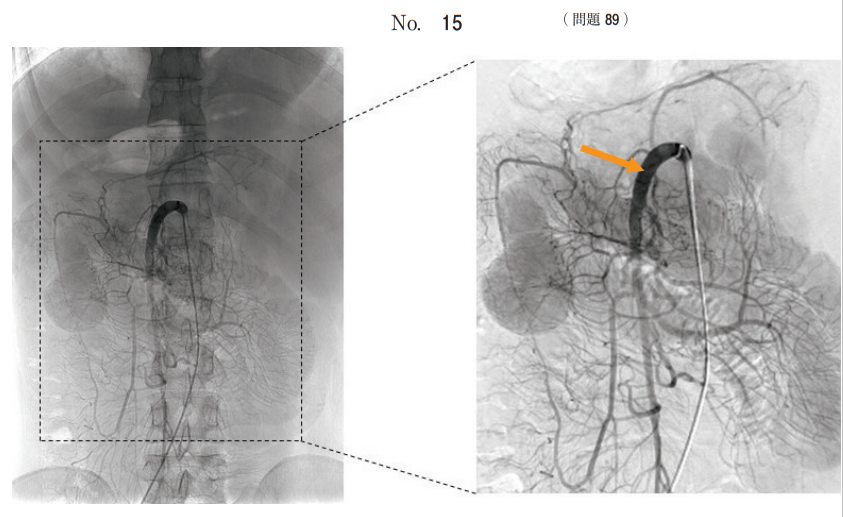

午後/問題89

腹部の血管造影写真(別冊No. 15)を別に示す。

矢印で示すのはどれか。

1.脾動脈

2.総肝動脈

3.左胃動脈

4.腹腔動脈

5.上腸間膜動脈

答え

5